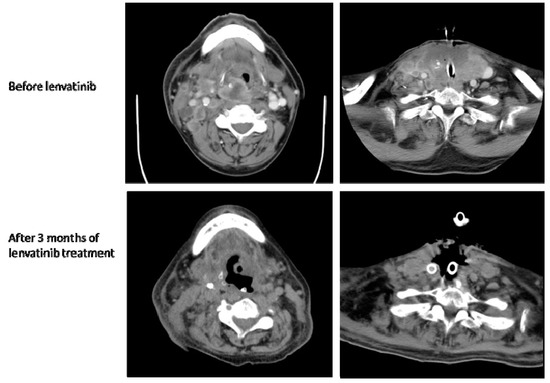

2.2. Case 2